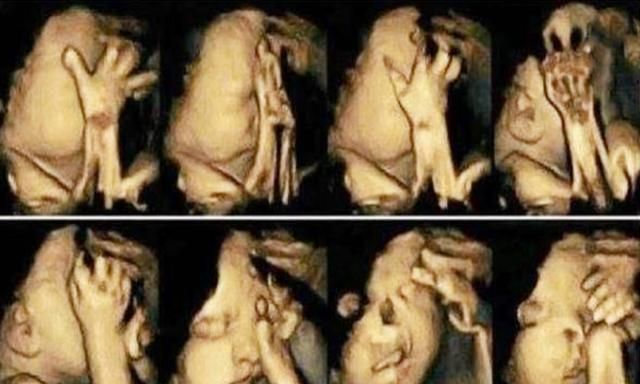

等小丽做B超的时候,通过电脑的屏幕医生对他说,孩子在不停的动,看不清楚孩子的另外半边。小丽看到后心里美滋滋地,觉得孩子是个聪明的孩子,这么小就这么爱表现。

这个时候医生让小丽出去走一走,等孩子把正脸露出来再来复查,小丽出去走了一圈,回来检查时,屏幕上出现了孩子的正脸,正冲着屏幕“做鬼脸”呢。

小丽很高兴,医生却说这孩子不能要有明显的唇腭裂。医生解释到孩子多动不一定是好事,有可能是他不舒服。小丽却以为是孩子活泼的表现,现在还是存在着心理缺陷。医生建议小丽想清楚了,如果生下来就要做好做大手术的心理准备,还不一定能恢复到正常的面容。